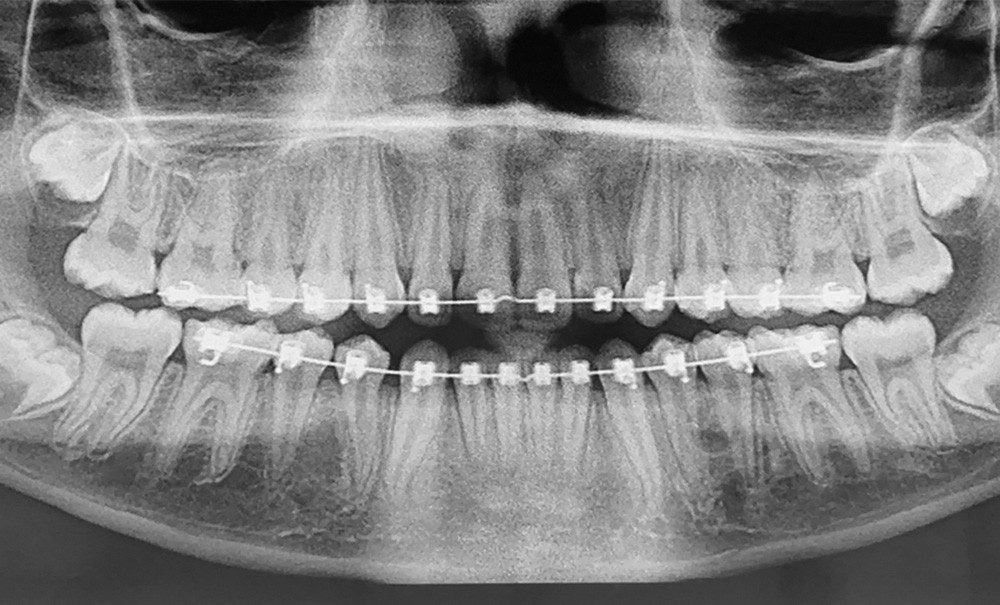

Le premier patient, âgé de 12 ans, est en cours de traitement…